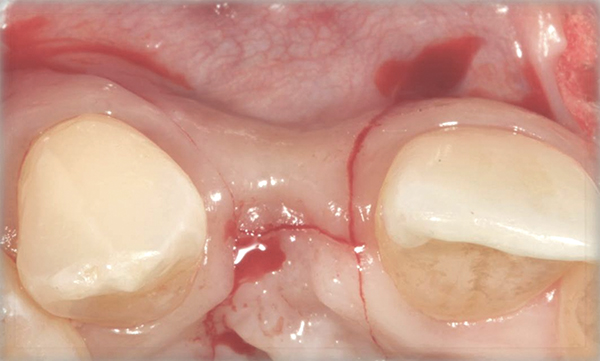

Fig 11. A horizontal releasing incision across the edentate ridge; it terminates 1 mm from the adjacent teeth.

Figure 11